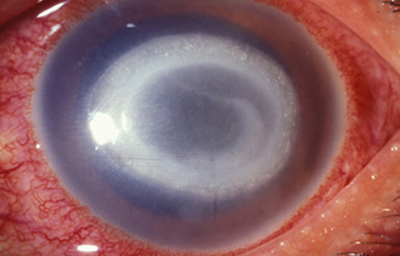

Superficie corneal irregular y grisácea, (Fig. 1, 2) con opácidades granulares en parche y formación de líneas epiteliales elevadas de aspecto granular (Fig. 3), que pueden arborizar dando imágenes de pseudodendritas. Opacidades superficiales satélites. (Figura 4) Inyección ciliar. Ulceración epitelial variante. (Figura 5).

Fig. 3 Líneas epiteliales elevadas. Síntomas de 40 días evolución